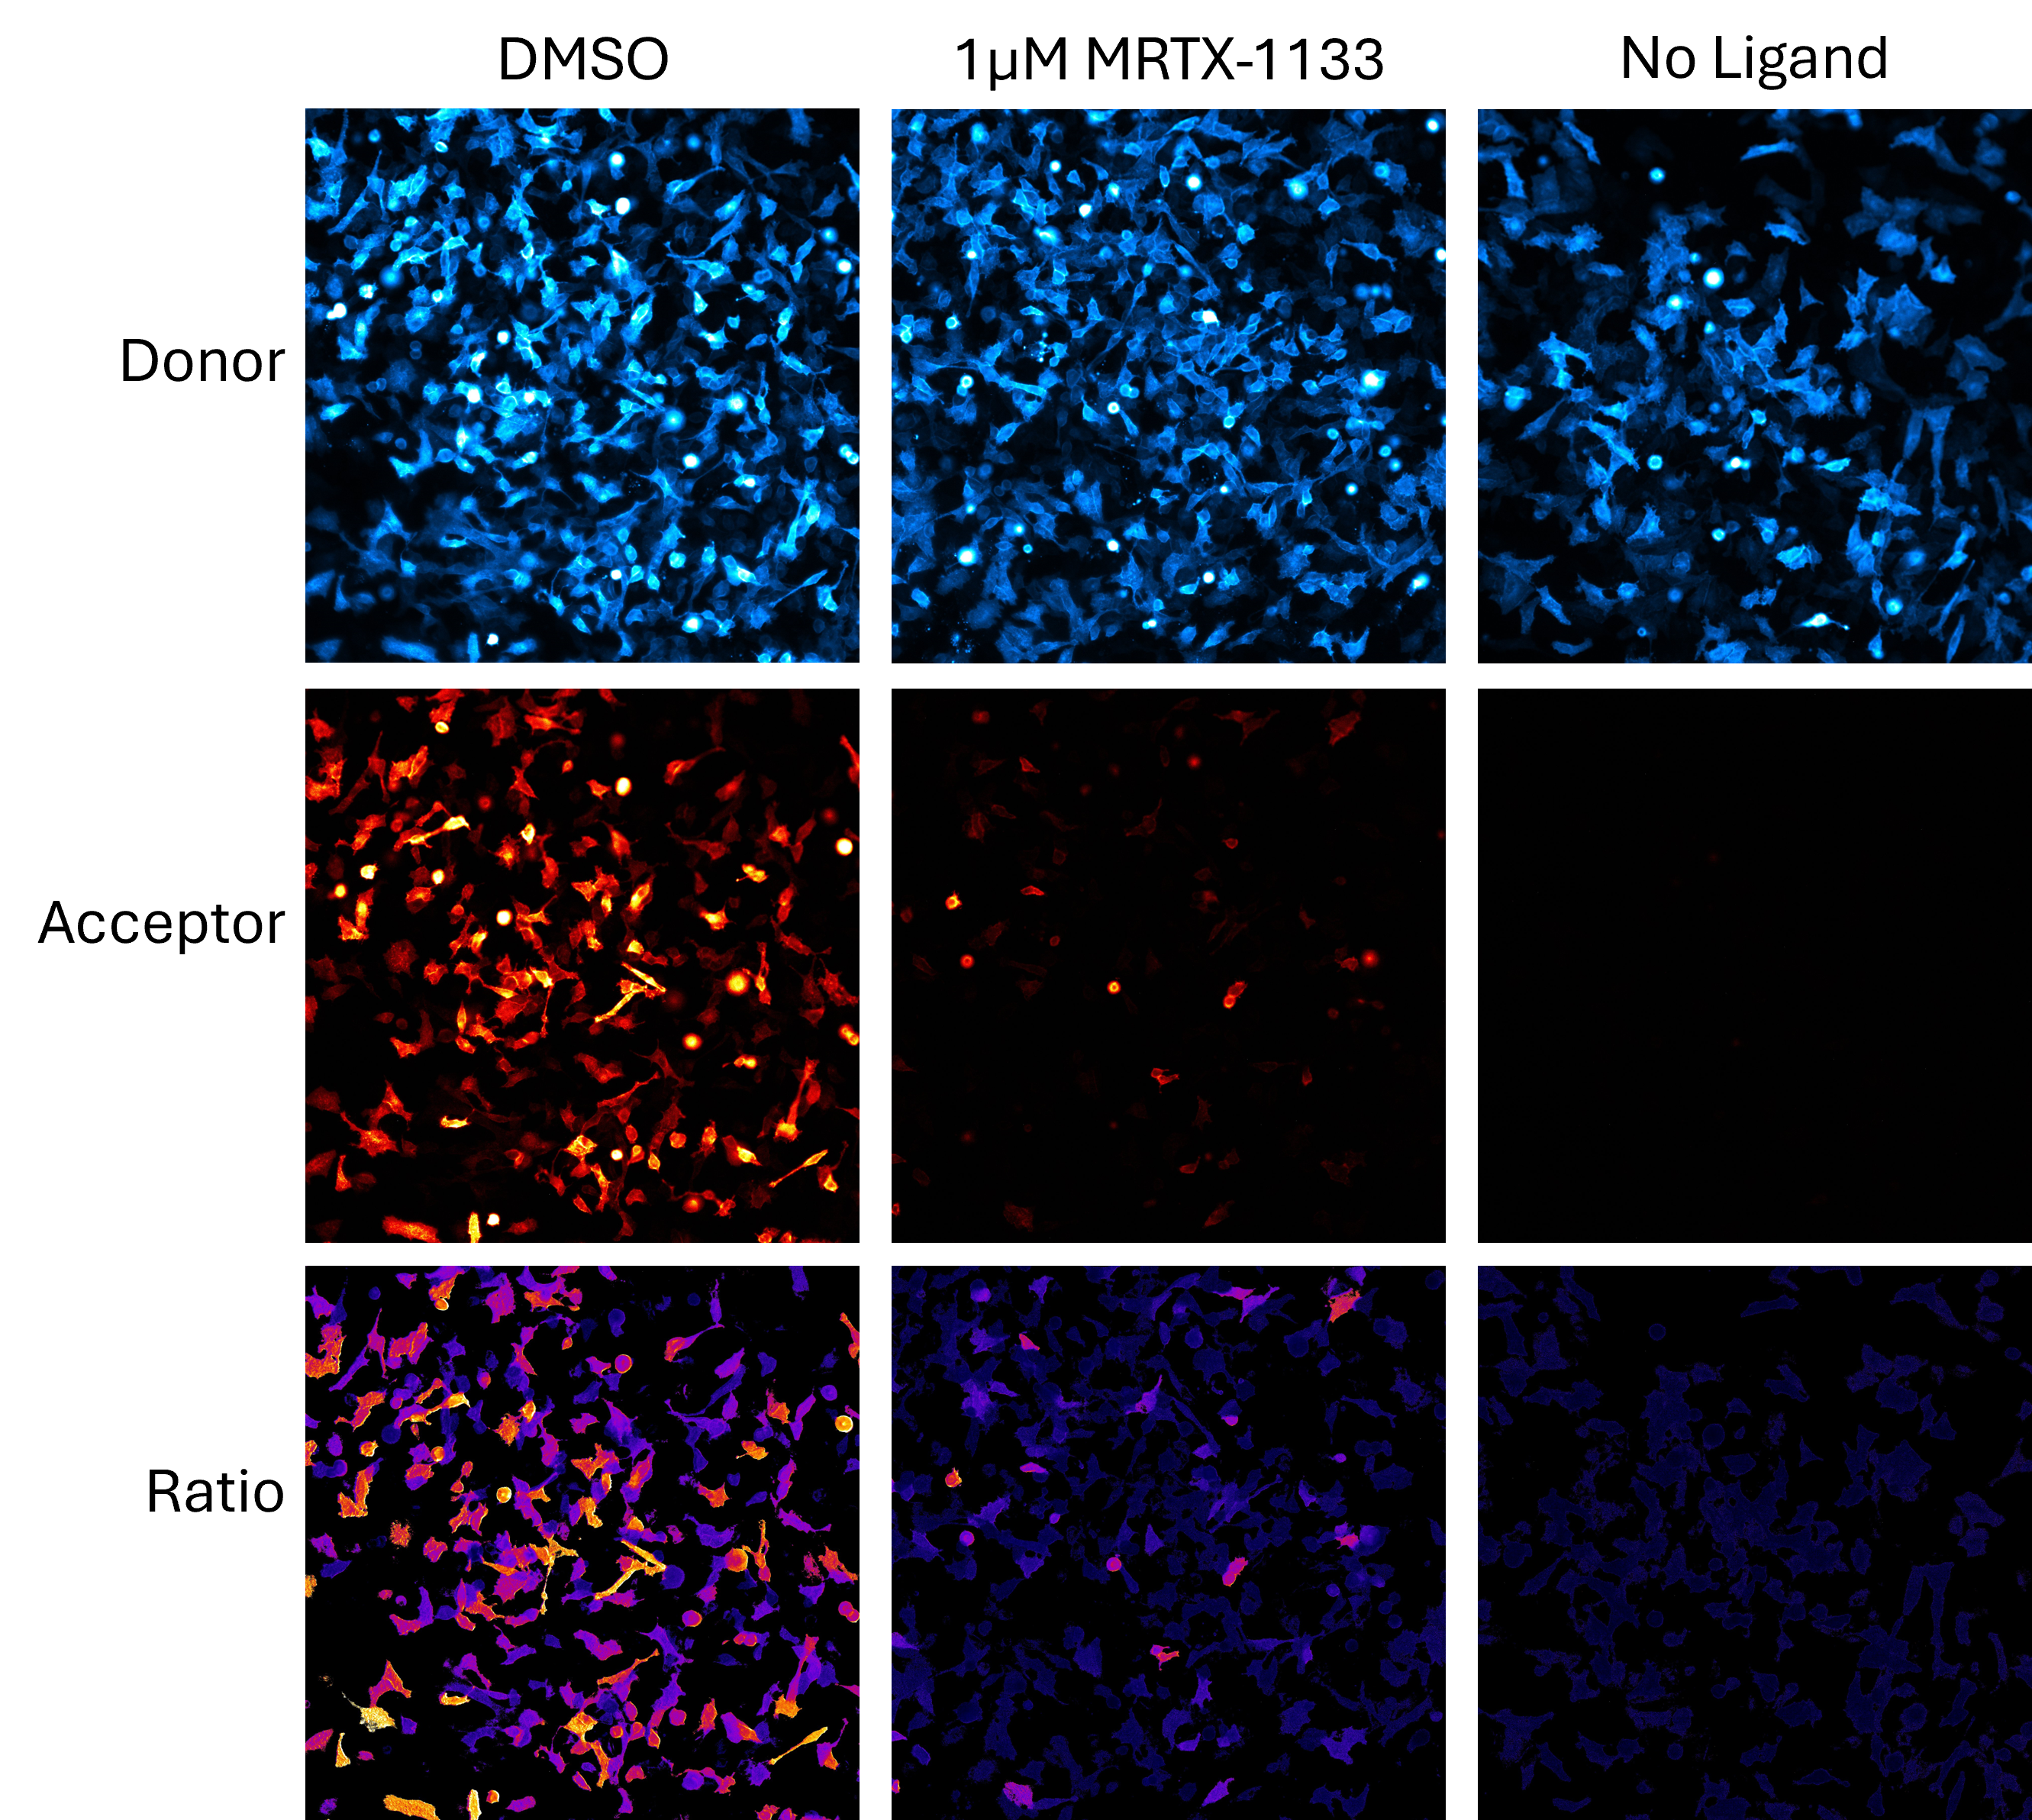

To determine what this treatment looked like on a cell-to-cell basis, images were then captured after cells were treated with MRTX-1133. HeLa cells were seeded in T75 flasks and transfected with a KRAS G12D–CRAF BiBRET construct using FuGENE® HD. The next day, transfected cells were plated into 8-well ibidi glass-bottom microchambers and incubated overnight. On day 3, treatments included HaloTag® NanoBRET® 618 Ligand alone or with MRTX-1133, and DMSO controls, followed by a 4-hour incubation. Live-cell imaging was performed using NanoBRET® NanoGlo® substrate. Filtered luminescence images were captured on the GloMax® Galaxy Bioluminescence Imager using 120s exposures and filtered channels. Images are shown in Figure 5.

To evaluate any bleed through of the donor signal into the acceptor channel, cells were tested without the HaloTag® ligand, as shown in column 3 of Figure 5. Control cells treated with DMSO produced bright and consistent donor and acceptor signals, with a BRET ratio indicating strong energy transfer between KRAS and CRAF. Upon treatment with 1µM MRTX-1133 for four hours, there was a significant reduction in the acceptor signal while the donor signal remained unaffected. This shift in the BRET ratio—leaning heavily towards the donor signal— is shown in the bottom row with a much darker image of cells. This reduction in the BRET ratio suggests that KRAS expression persisted, but the protein:protein interaction with CRAF had been disrupted.

One of the key advantages of using the GloMax® Galaxy is the ability to distinguish between cells based on their individual responses. In this experiment, the imaging system allowed us to analyze the ratio of energy transfer at the single-cell level, providing deeper insights into how each cell responded to MRTX-1133 treatment. For example, some cells do show low levels of acceptor signal, suggesting they did not respond to the dose of MRTX-1133 selected. This highlights how subtle differences in cell responses can be missed when taking a snapshot of a global cell population.